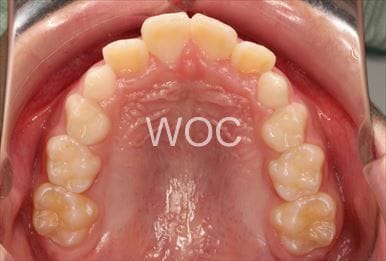

治療後1

-

治療後2

-

治療後3

-

治療後4

-

治療後5

- 年齢:20歳女性

- 主訴:出っ歯が気になる

- 基本矯正料金:120万円

- 治療期間:1年7ヶ月

- 抜歯部位:上顎両側第一小臼歯